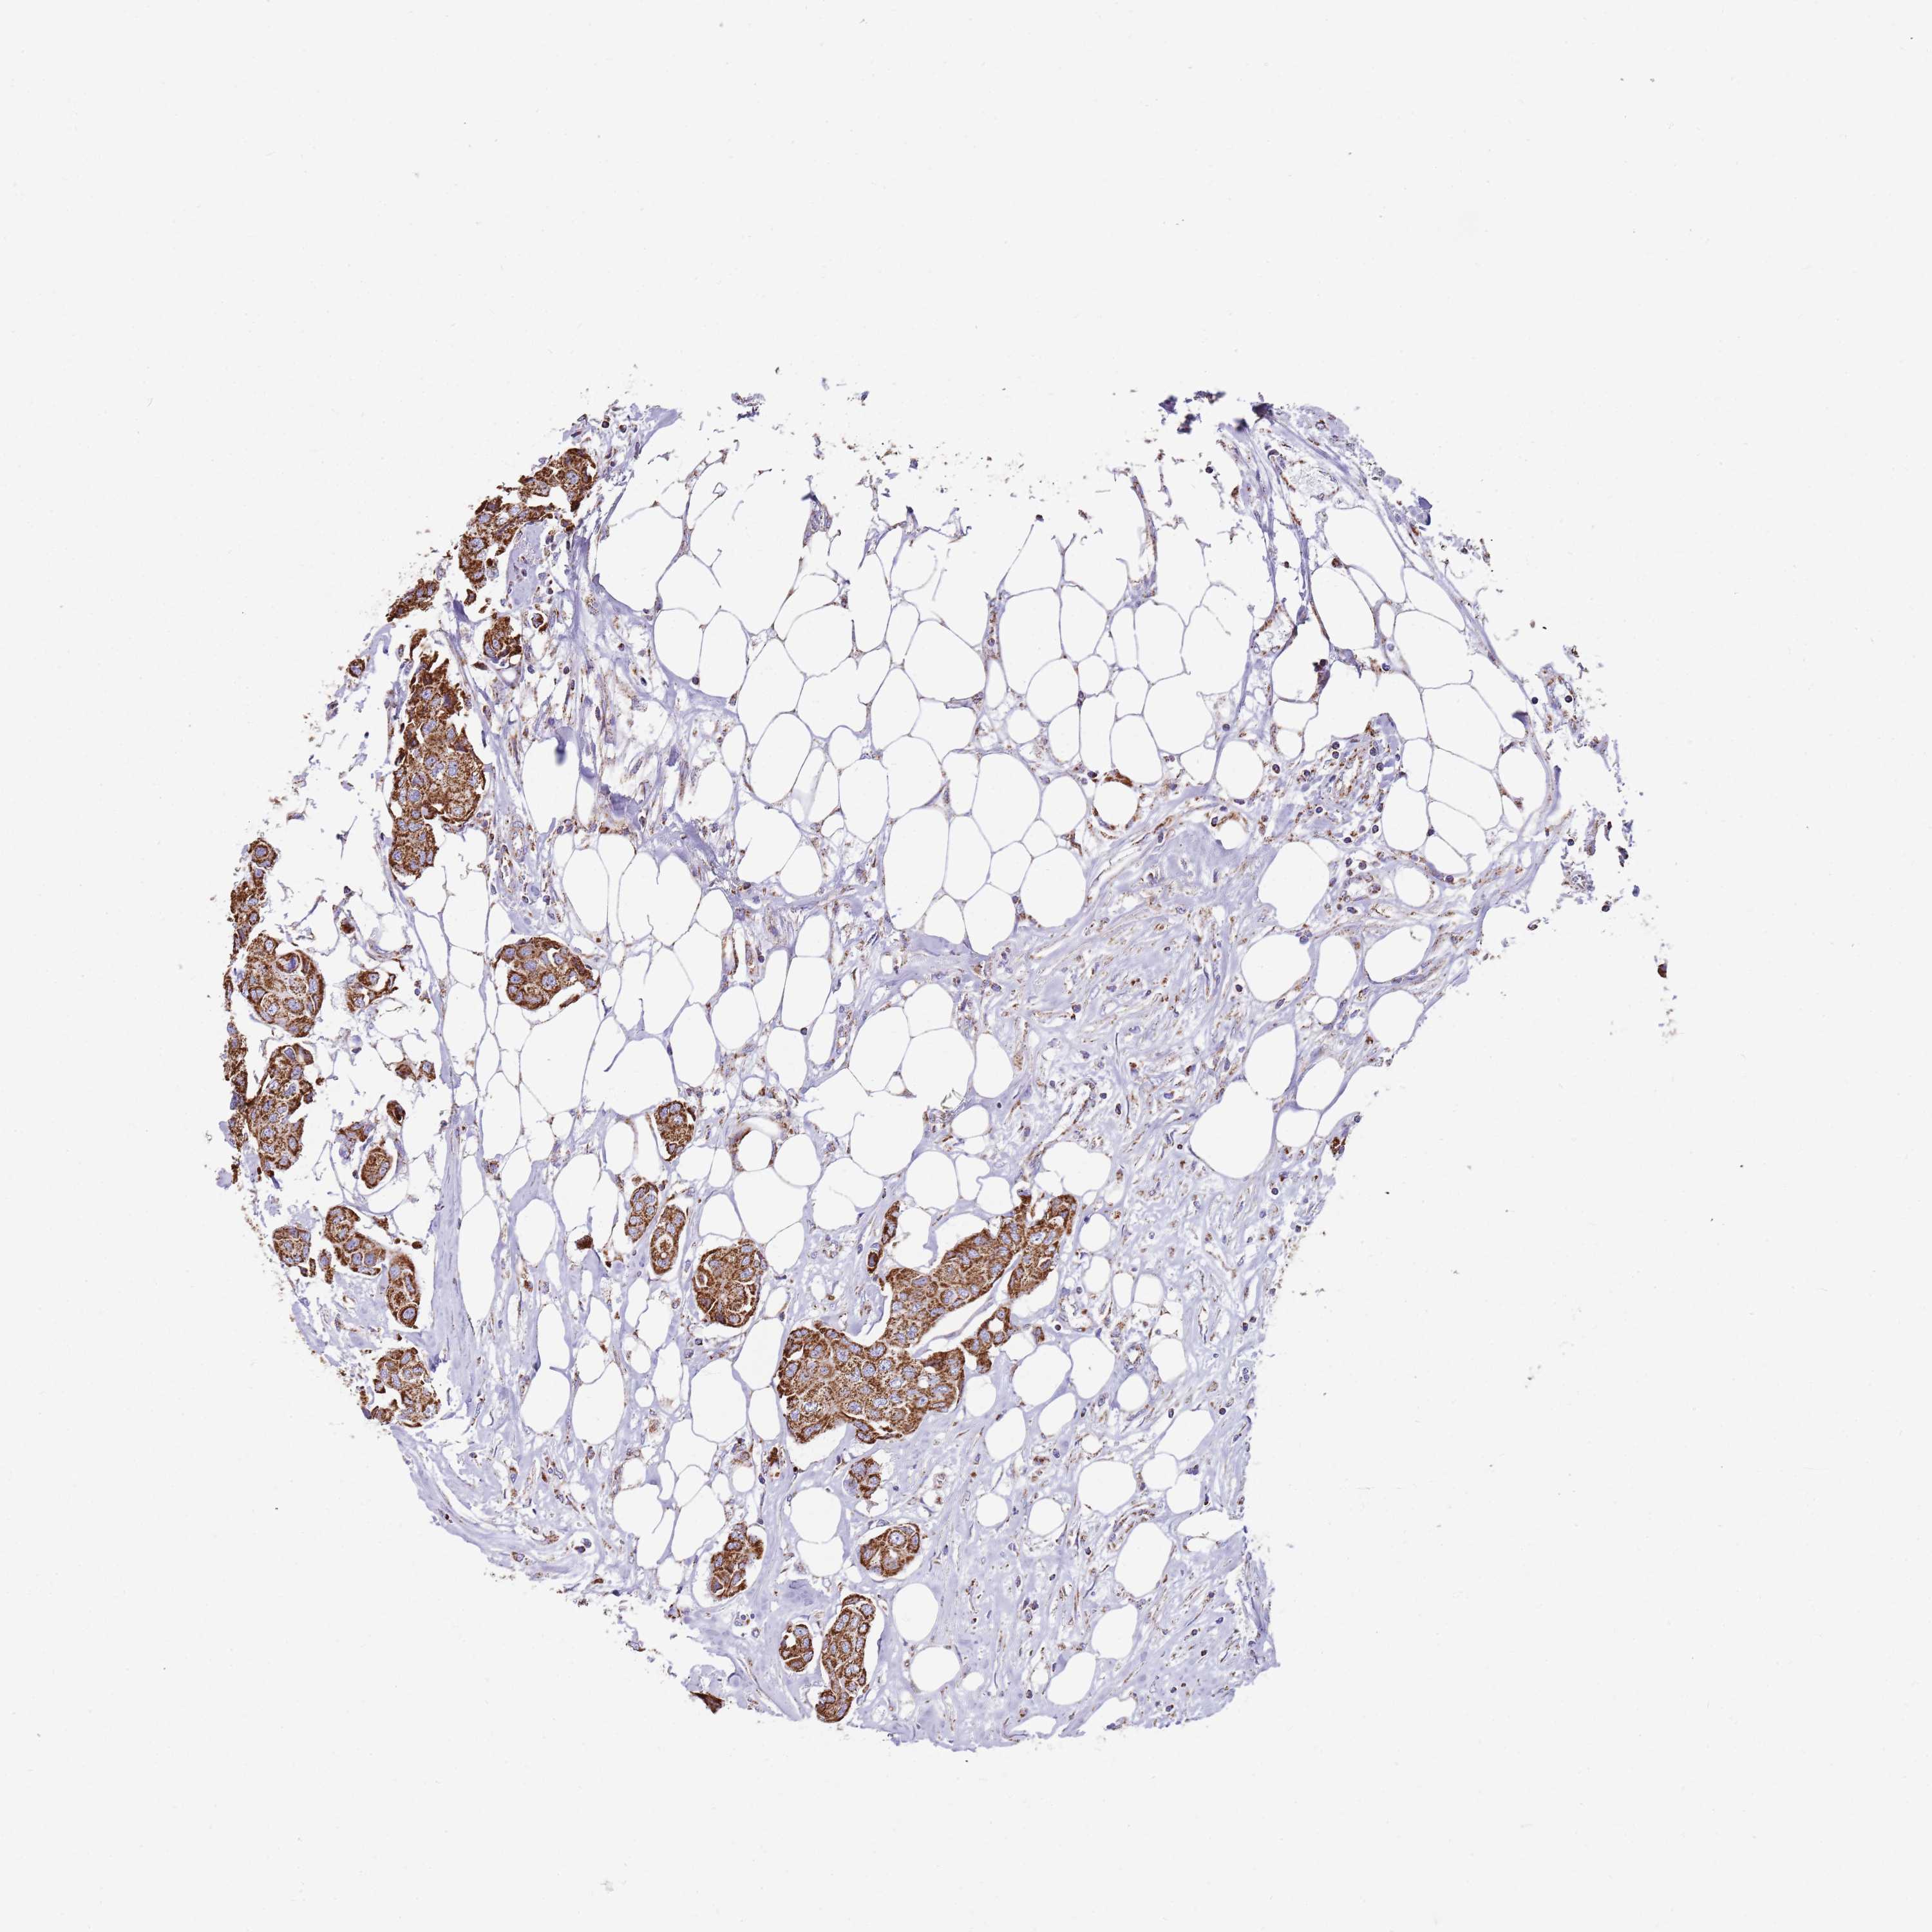

CANCER BREAST CANCER Show tissue menu

BRCA TCGA BRCA VALIDATION PROTEIN EXPRESSION